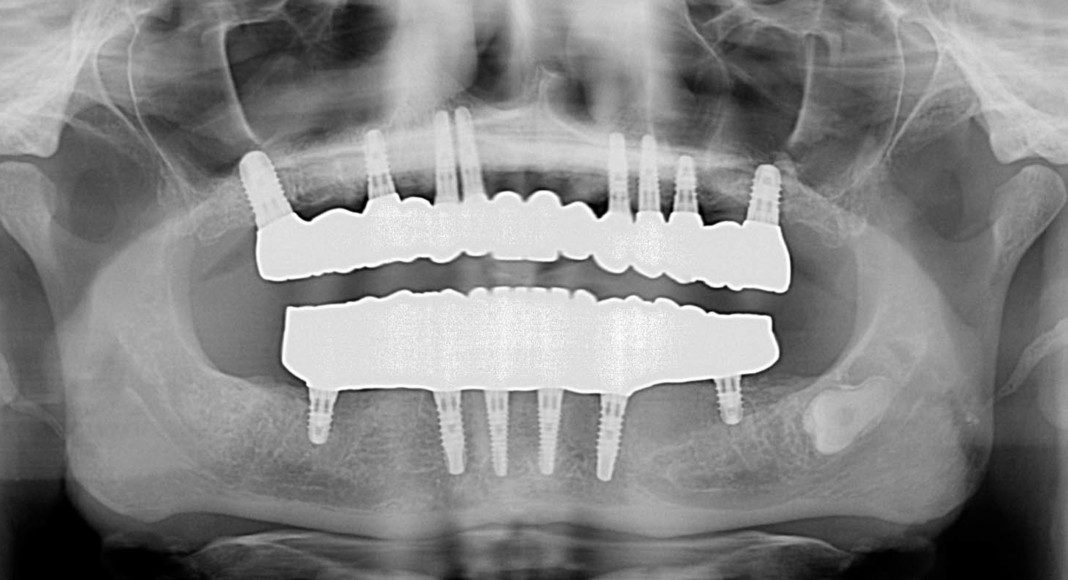

Panoramic radiograph of patient. Like so many patients, she had too many teeth for a small mouth. There was crowding and impacted teeth.